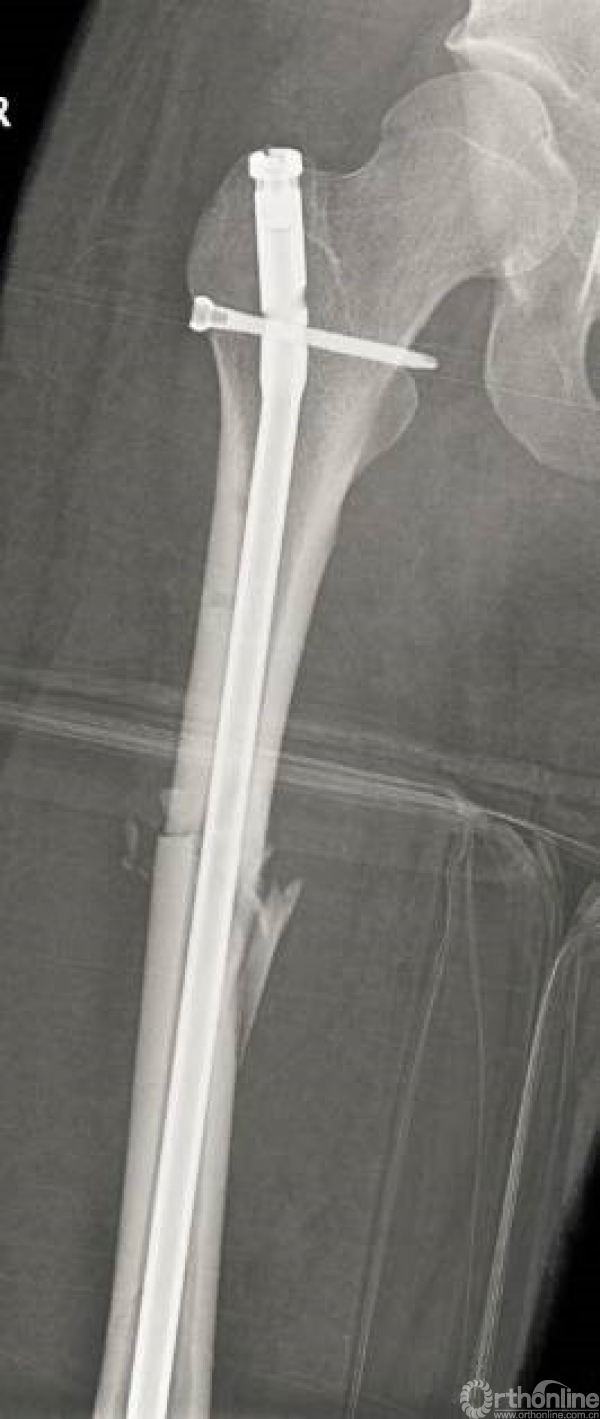

术后